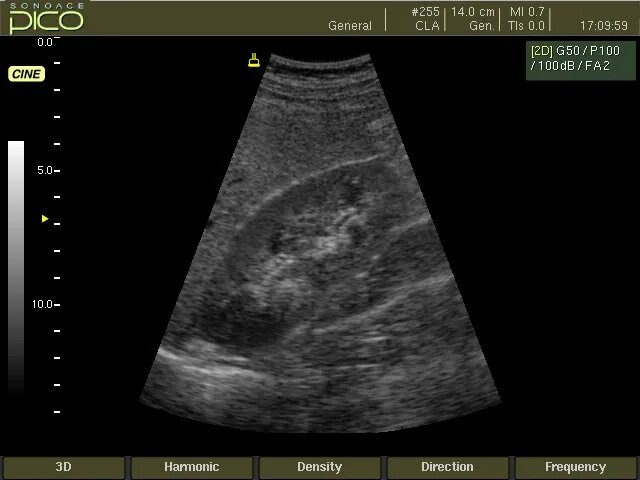

Бочкарева узи